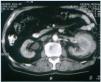

Hombre de 77 años de edad con antecedentes de hipertensión arterial de 30 años de evolución, que fue remitido a nuestro hospital para seguimiento por insuficiencia renal crónica. Cuatro años antes había sido diagnosticado, por endoscopia digestiva alta, de esófago de Barrett y úlcera duodenal con estenosis pilórica. En la biopsia del esófago se observó esofagitis con koilocitosis. El test de la ureasa en la biopsia fue negativo, pero recibió tratamiento específico para erradicación de H. pylori. En ese momento, los datos de laboratorio revelaron: hematocrito 40%, hemoglobina 12,5 g/dl, leucocitos 5.380/ml, con recuento diferencial normal y una velocidad de sedimentación globular (VSG) de 20 mm/h (normal, 15-30 mm/h). Las proteínas plasmáticas totales fueron de 5 g/dl y la albúmina de 3,1 g/dl. El análisis de orina fue normal y la creatinina sérica varió desde 1,2 hasta 1,4 mg/dl. Continuó recibiendo tratamiento con omeprazol y 16 meses después un estudio con bario del tracto gastrointestinal superior fue normal. En el momento del ingreso la exploración física fue normal. Los datos de laboratorio mostraron: hematocrito 34,5%, hemoglobina 11 g/dl, leucocitos 5.950/ml con fórmula normal, plaquetas 161.000/ml y VSG 100 mm/h. La coagulación sanguínea fue normal. Un análisis de orina reveló un sedimento normal y proteinuria de 1,2 g/24 h. La urea sérica fue de 70 mg/dl, la creatinina de 2,2 mg/dl y el aclaramiento de creatinina 45 ml/min. Las proteínas plasmáticas totales fueron de 9,6 g/dl, albúmina 4,1 g/dl y gammaglobulina 3,5 g/dl (con un pico monoclonal). Los valores de inmunoglobulinas medidas por nefelometría fueron IgM 4.640 mg/dl (normal, 38-231 mg/dl), IgG 858 mg/dl (normal, 650-1.700 mg/dl) e IgA 168 mg/dl (normal, 103-568 mg/dl), kappa 641 mg/dl (normal, 170-370 mg/dl), lambda 106 mg/dl (normal, 90-210 mg/dl). Por inmunofijación se detectó en el suero un pico monoclonal IgM kappa. Las crioglobulinas en suero fueron negativas y la proteinuria de Bence-Jones fue positiva. Otros datos de laboratorio mostraron: PCR 4,9 mg/dl, beta-2-microglobulina 4,9 mg/l, LDH 286 U/l, calcio 9,9 mg/dl y fosfato 3,2 mg/dl. Las serologías para el virus de Epstein-Barr y el virus de la hepatitis C fueron negativas. En la ecografía abdominal se detectó una masa sólida en el riñón izquierdo. Las radiografías y gammagrafía óseas no revelaron ninguna anormalidad. Una tomografía computarizada (TAC) toracoabdominal reveló una masa de unos 7 cm situada en la parte media del riñón izquierdo (figura 1). No hubo evidencia de adenopatías. En el aspirado de médula ósea se detectó un patrón normocelular y reveló un 12,5% de células plasmáticas atípicas. La citometría de flujo de la médula ósea mostró un 3% de linfocitos T policlonales y un 1% de linfocitos B policlonales. Las células plasmáticas fueron CD38++, CD138—, CD19+, CD45+, CD56—, CD117— y kappa monoclonal.

Figura 1. TAC mostrando el crecimiento tumoral a través de la corteza del riñón izquierdo.